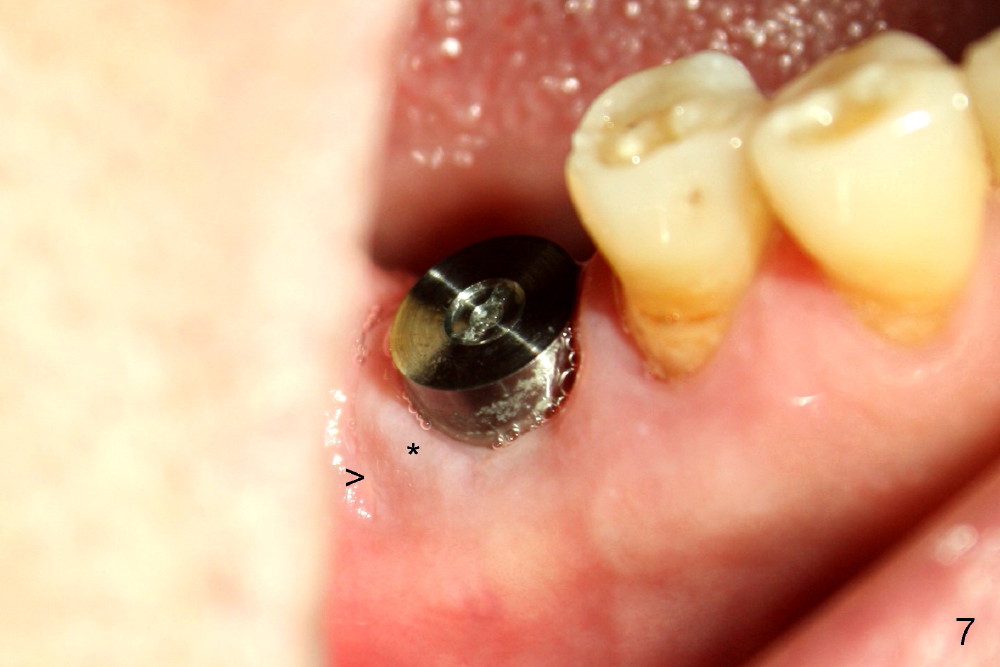

Twelve days postop, the DB (Fig.7 >) and DL (Fig.8 <) sockets have healed. * in Fig.7 used to be the furcal gingiva.